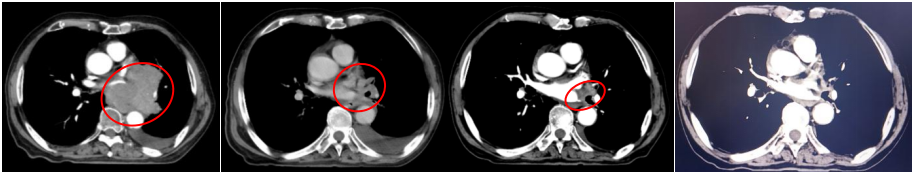

2022-07-19(2周期后)胸部、全腹部增强CT:1.肺癌复查,较前(2022-05-23)左肺门占位明显减小,左肺下叶远端阻塞性改变较前范围减小;2.双肺肺气肿;3.左侧胸腔积液,累及左侧胸膜可能,较前略增多;4.心包少量积液,较前增多;5.肝内多发囊肿;右肾上极小囊肿;6.肝左叶内小海绵状血管瘤可能;7.前列腺增大伴钙化。

2022-09-30(4周期后)胸部、全腹部增强CT:1.肺癌复查,较前(2022-07-19)左肺门占位减小,左肺下叶远端阻塞性改变较前范围减小;2.双肺肺气肿;3.左侧胸腔积液,累及左侧胸膜可能,较前减少;4.心包少量积液,大致同前;5.肝内多发囊肿;右肾上级小囊肿;6.肝左叶内小海绵状血管瘤可能;7.前列腺增大伴钙化。

2022-11-21(6周期后)胸部、全腹部增强CT:左肺门占位较前(2022-09-30)减小,左肺下叶远端阻塞性改变较前变化不大;左侧胸腔积液,累及左侧胸膜可能,较前减少;心包少量积液,大致同前。

疗效评估:PR(接近CR)。